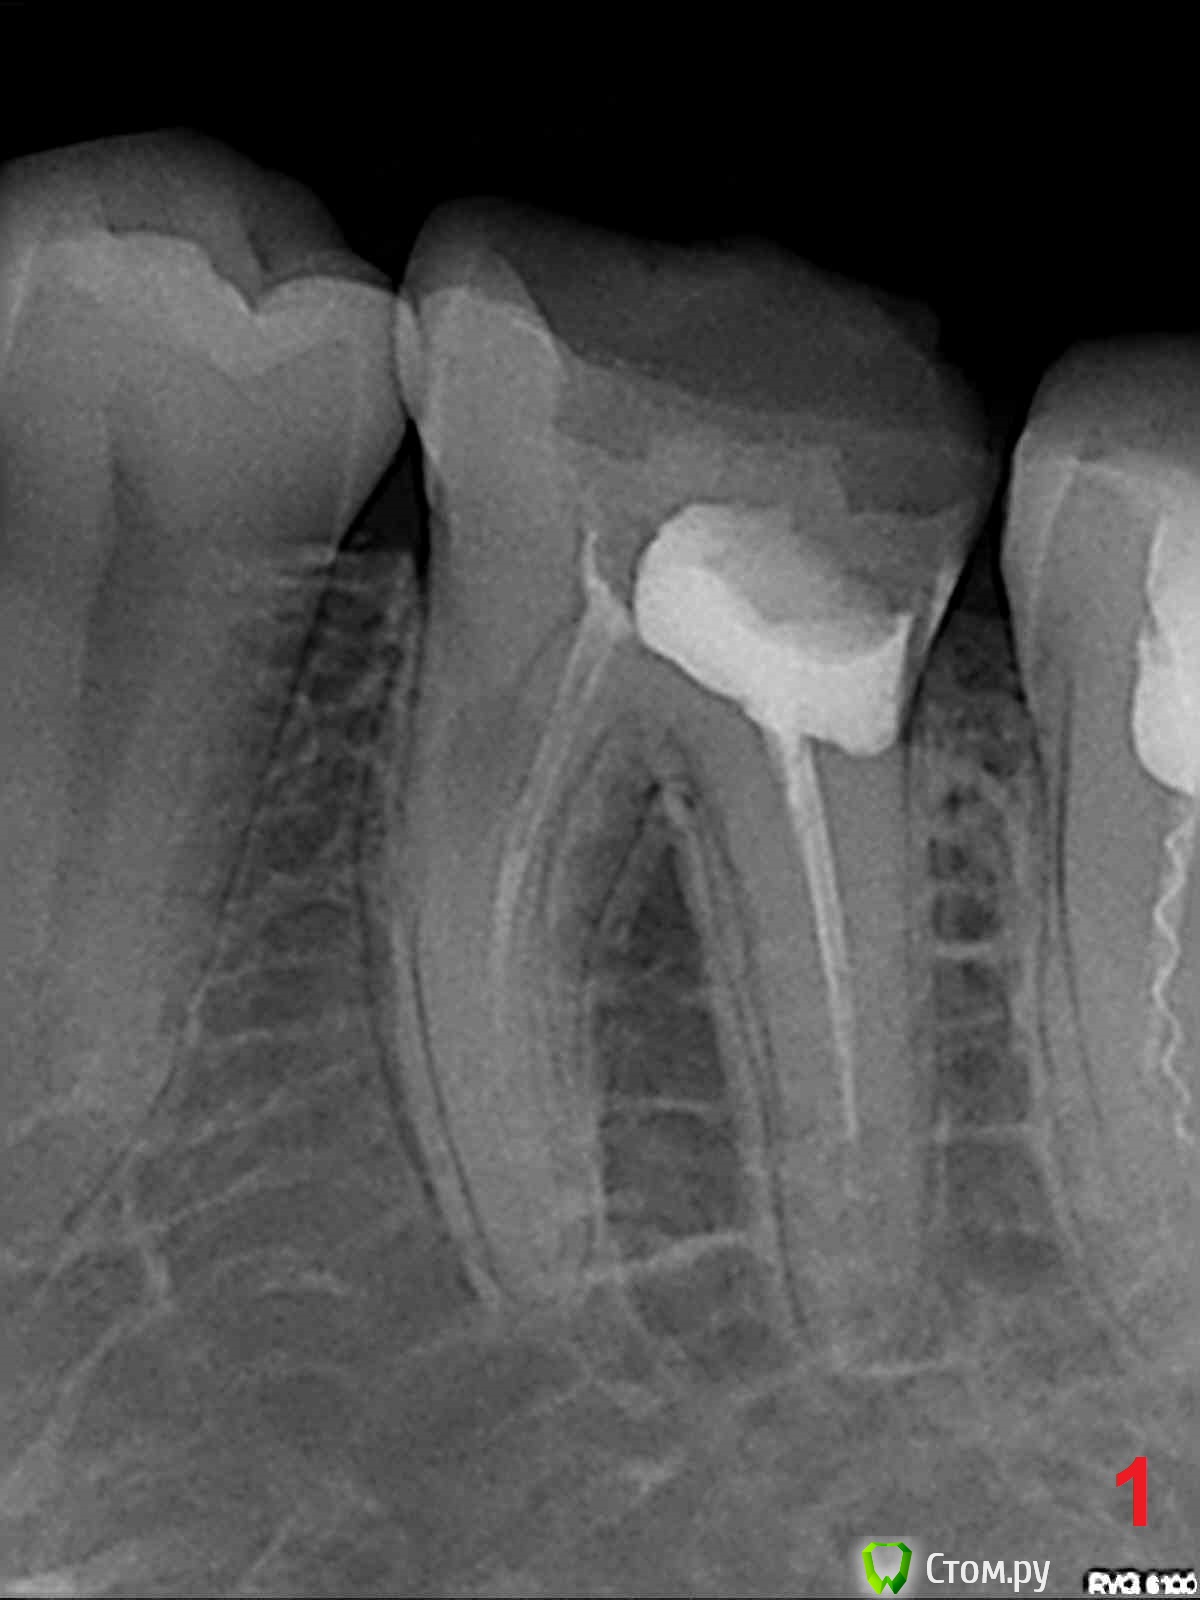

edw Опубликовано 16 июня, 2014 Поделиться Опубликовано 16 июня, 2014 Здравствуйте.Год назад в стоматологии прочистили каналы 36 (вроде) зуб, снимок 1. Месяцев через 7 после лечения появилась нарастающая все сильней боль, в итоге нажимать на зуб даже языком было очень больно. Пошел в эту же стоматологию, этот же врач переделал зуб по гарантии, снимок 2. Было больновато, как будто снова нервы не удалили до конца в прошлый раз. После перелечивания прошло уже месяца 2-3, зуб побаливает перидически, ноет, на горячее реагирует, например. Прошу знающих людей посмотреть снимки, сильно ли все плохо, и чем грозит? Хочу начать эпопею по возврату денег. 1 Ссылка на комментарий

red_butler Опубликовано 16 июня, 2014 Поделиться Опубликовано 16 июня, 2014 Если судить только по снимку - зуб нужно удалять, ввиду сильного разрушения, ниже уровня десны 1 Ссылка на комментарий